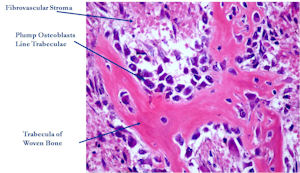

Microscopic Pathology

- Interlacing network of bone trabeculae in a loose fibrovascular stroma

- Prominent vessels

- Osteoblasts are plump, active, scattered mitotic figures

- Osteoblasts line up around periphery of trabeculae (Osteoblastic Rimming)

- Soft tissue component usually surrounded by shell of reactive bone or periosteum (Egg Shell Rim of Calcification)

- No cartilage production (as opposed to osteosarcomas that may contain areas of cartilage)